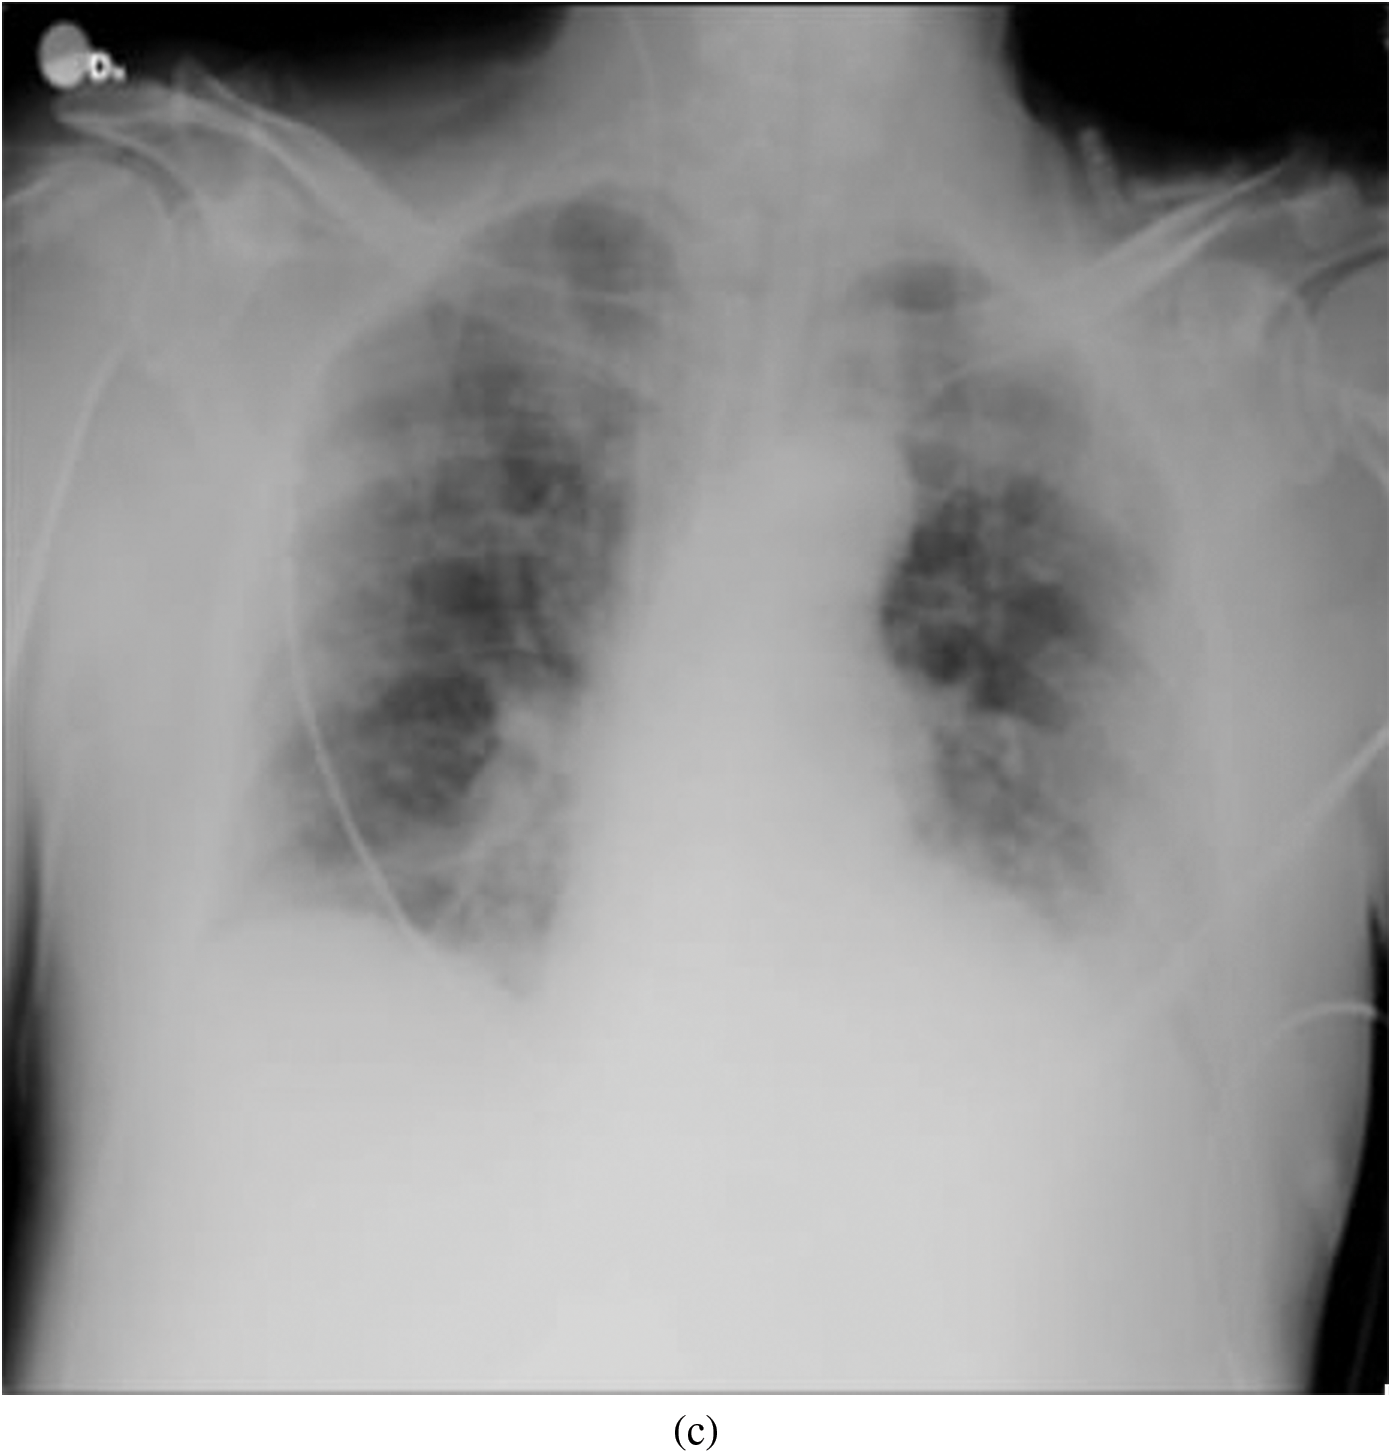

Representative images belonging to the normal, COVID-19, LO, and VP groups are shown in Figs. 2–5, along with their corresponding histograms. The images clearly depict variability in pixel intensities, particularly in and around the lung regions. The visibility of the rib cages is very obvious in the case of the normal and COVID-19 images as shown in Figs. 2a, 2b, 3a and 3b respectively compared to the LO and VP images in Fig. 4a, 4b, 5a and 5b. The visibility of lungs in COVID-19 patients is unclear. The histograms represent different perspectives, with varying distribution of intensities across the four categories, particularly COVID-19, indicating a large presence of high pixel intensities.

Figure 4: Representative image and its corresponding histogram depicting the distribution of pixel intensities of a Lung Opacity (LO) image